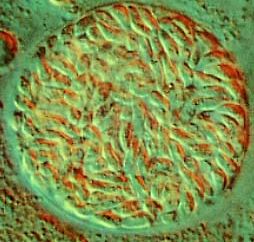

图1猫弓形虫卵囊

图2猫弓形虫包囊

图3猫弓形虫包囊